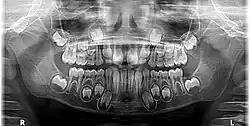

Radiographic appearance

On radiographs, enamel appears as the most radiopaque (white) structure due to its high mineral content.[19] Dentine and cementum are less radiopaque and are usually indistinguishable from each other.[19] The pulp chamber and root canals are radiolucent (dark), centrally located within the tooth structure. The periodontal ligament appears as a thin, radiolucent line between the root and the lamina dura.[19]

Figure 5: X-ray showing mixed primary and permanent teeth of an eight-year-old boy